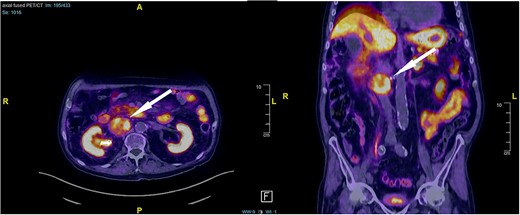

An 87-year-old male Caucasian patient with a history of cardiac co-morbidities, diabetes mellitus type 2, and chronic kidney disease stage 4 was referred to our hospital for clinical evaluation and a non-contrast abdominal–pelvic CT scan because of right side pain with a history of kidney stone disease, with recurrent ureteral stones. The CT scan showed a small distal ureteral stone on the right side without the need for surgical intervention. Incidentally, he had a retroperitoneal mass (4.4 × 4 × 4 cm) posterior to the inferior vena cava, with compression on the inferior vena cava and the right renal artery (Fig. 1). Our radiologist classified this unexpected incidental finding as a possible neuroendocrine tumor, with the recommendation to perform a DOTATE-PET/CT scan. The DOTATE-PET/CT showed a sizeable retrocaval mass with edge-accentuated radionuclide storage, compatible with a paraganglioma or a lymph node metastasis of a neuroendocrine tumor (Fig. 2). The ultimate etiology remained unclear, despite the radiological scans. Our blood tests showed a normal level of hormones in the blood and urine, excluding hormonally active tumors. The only noticeable value in the blood was the elevated creatinine as a part of the chronic kidney disease. One of our assumptions was that the tumor compression on the renal artery impacts the patient’s kidney function. The patient reported no remarkable symptoms.

DOTATE-PET/CT: sizeable retrocaval mass with edge-accentuated radionuclide storage, compatible with a paraganglioma or a lymph node metastasis of a neuroendocrine tumor (arrow).